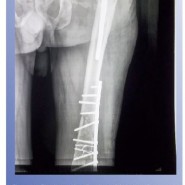

tenotomy done. Next he was positioned laterally and the fracture was

fixed with heavy duty broad dynamic compression plate and screws. The

wound was temporarily closed. Now through the previous scar via

reduce the same. At one year when he was walking unaided and his X-rays

showed that fracture had well united his SF-36 score was PCS – 49.6 and

MCS – 51.9.